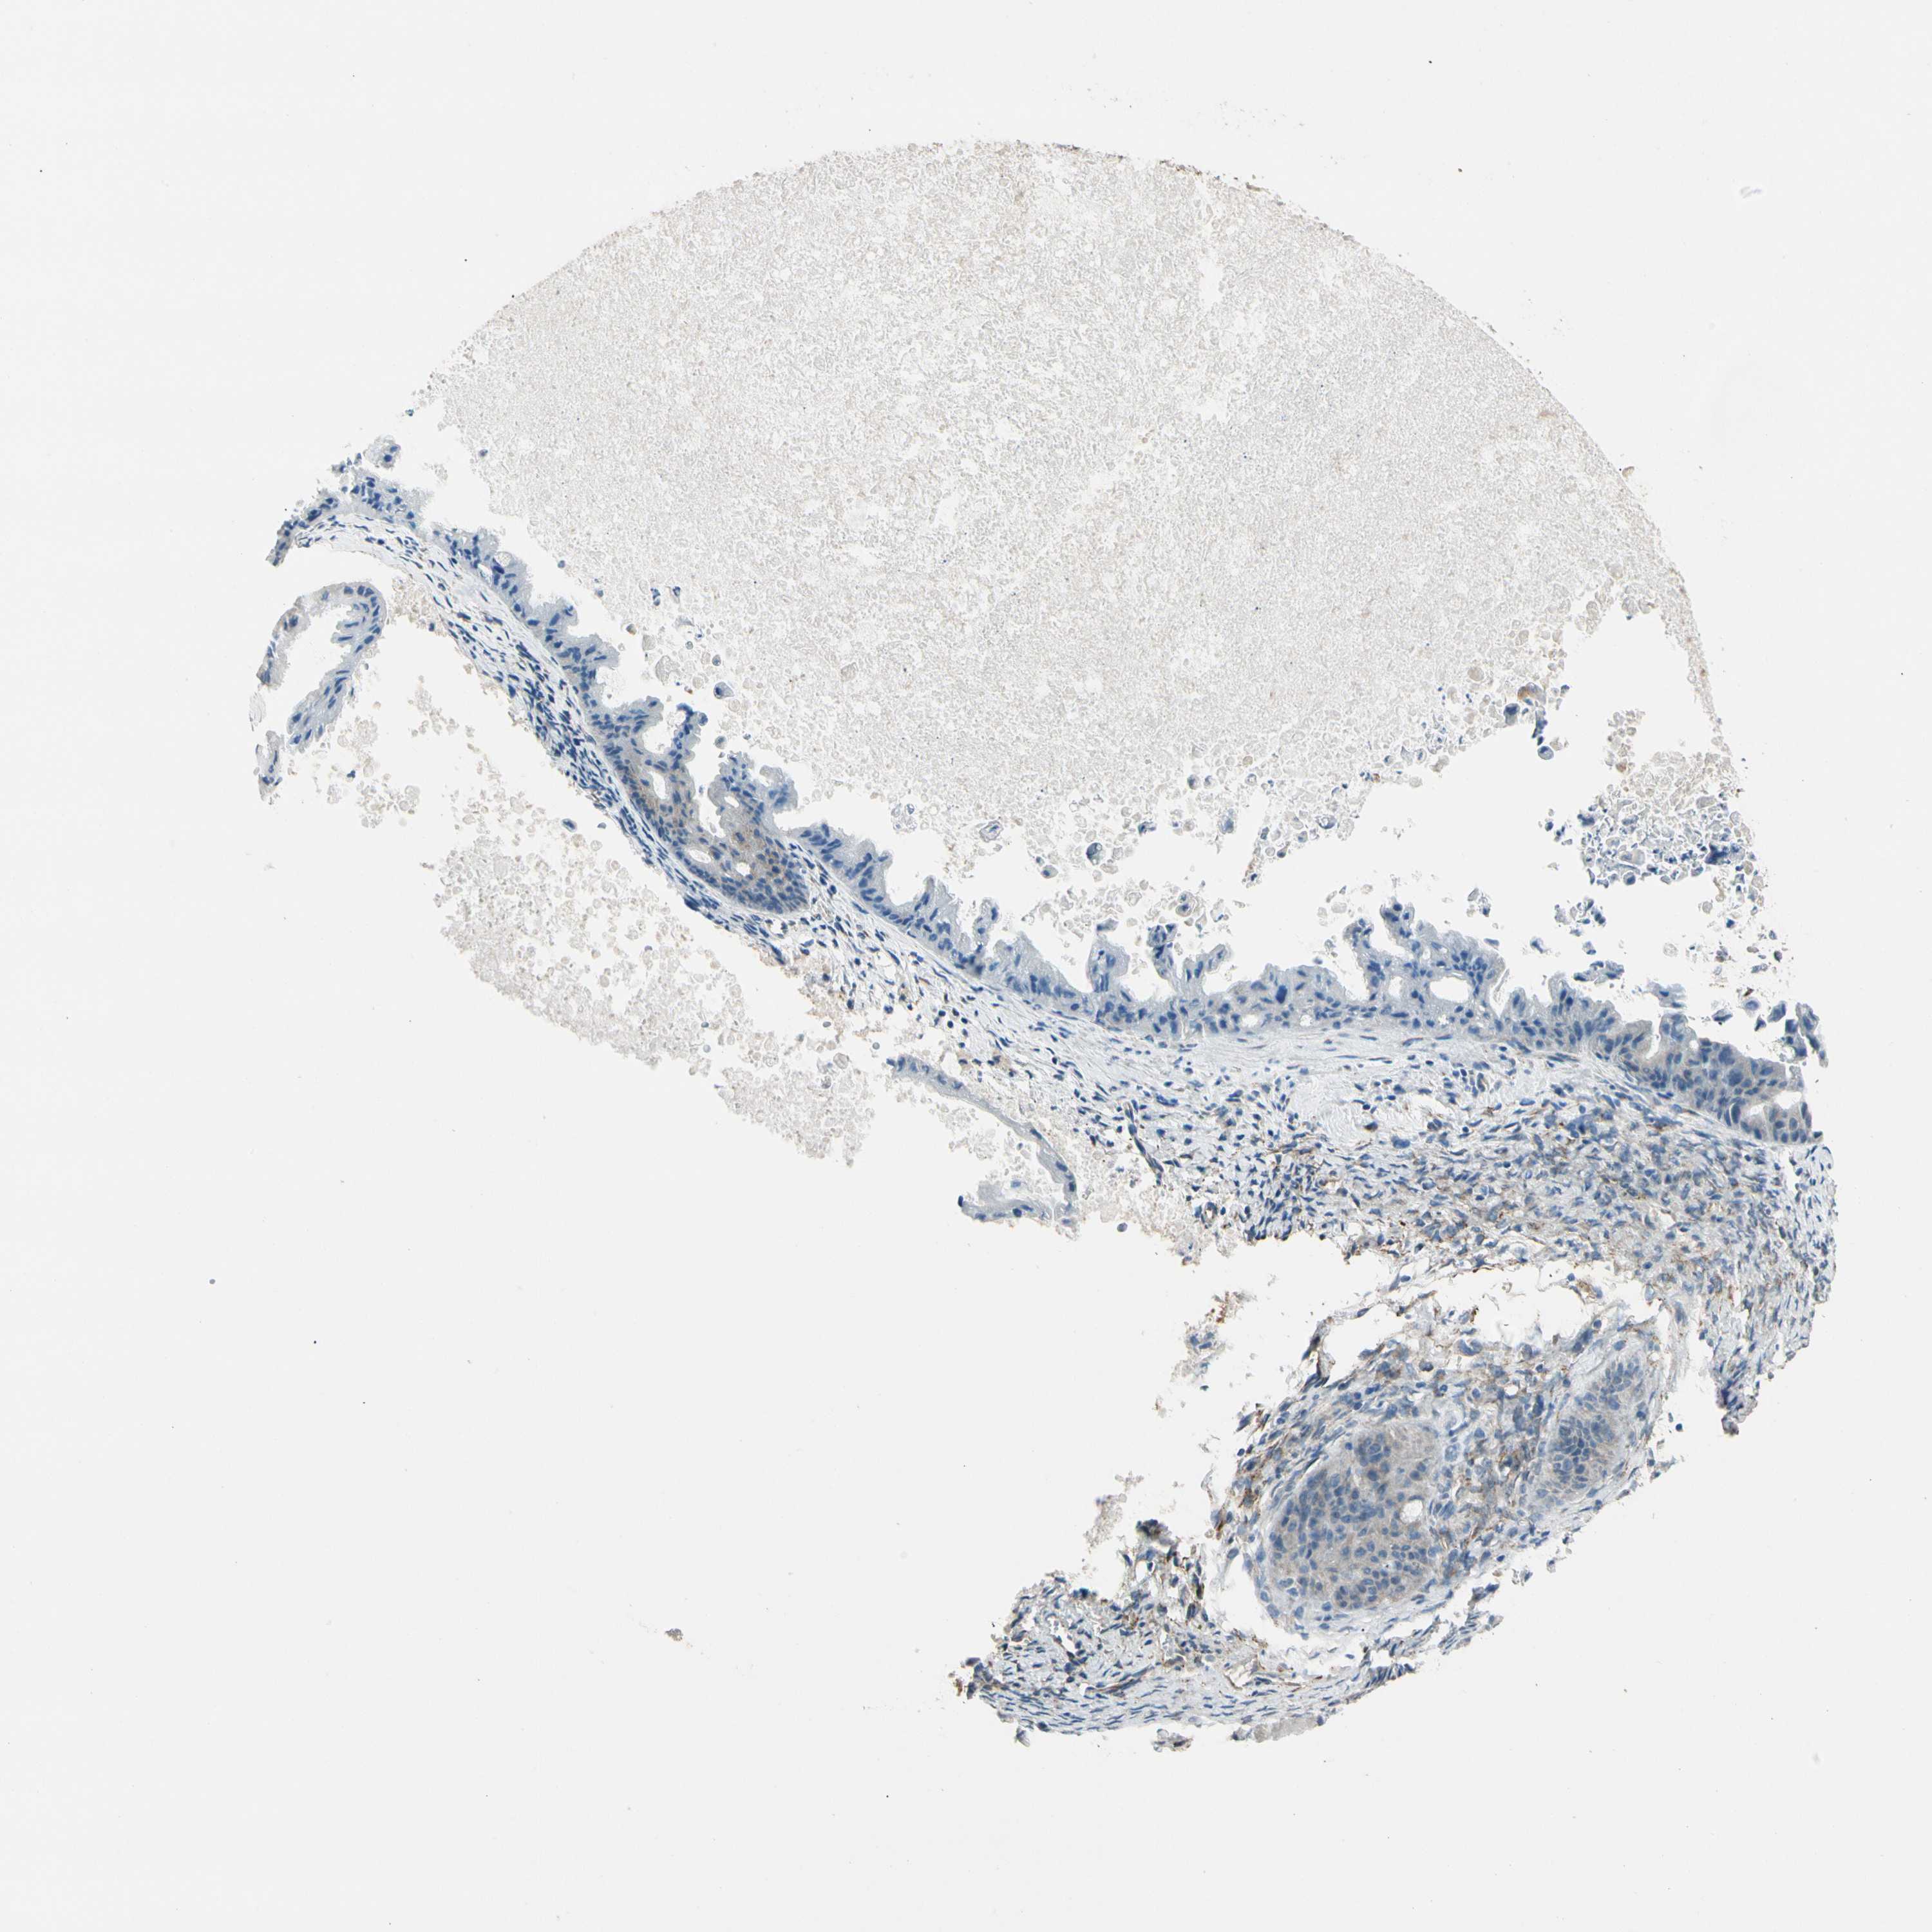

OVARIAN CANCER - Protein expressioni

A mouse-over function shows sample information and annotation data. Click on an image to view it in a full screen mode. Samples can be filtered based on level of antibody staining by selecting one or several of the following categories: high, medium, low and not detected. The assay and annotation is described here.

Note that samples used for immunohistochemistry by the Human Protein Atlas do not correspond to samples in the TCGA dataset.

Antibody stainingi

Antibody staining in the annotated cell types in the current human tissue is reported as not detected, low, medium, or high, based on conventional immunohistochemistry profiling in selected tissues. This score is based on the combination of the staining intensity and fraction of stained cells.

Each image is clickable and will lead to virtual microscopy that enables deeper exploration of all samples and also displays staining intensity scores, fraction scores and subcellular localization as well as patient and tissue information for each sample.

Antibody HPA008707

Staining

Cystadenocarcinoma, serous, NOS

Carcinoma, endometroid

Cystadenocarcinoma, mucinous, NOS

Carcinoma, NOS